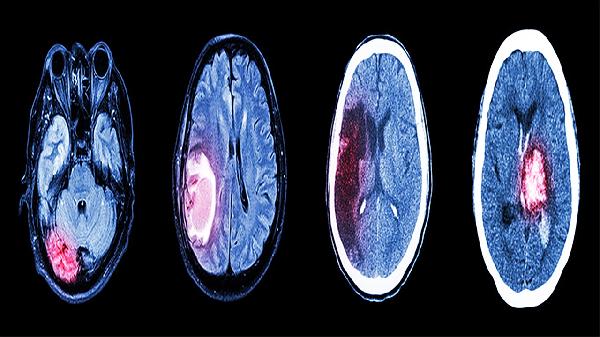

药物中的有效成分可减轻缺血再灌注损伤,保护神经细胞功能。对急性脑梗死后遗留的认知功能障碍、反应迟钝等有一定改善效果,常与奥拉西坦胶囊、吡拉西坦片等促智类药物联合应用。需注意肾功能异常者调整剂量。